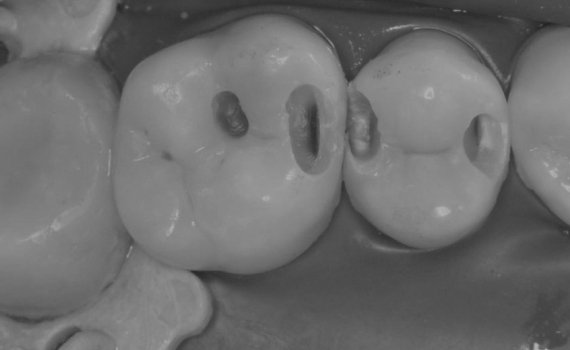

• Функциональная реставрация жевательных зубов с восстановлением окклюзии

• 2021 г. — Двухдневный курс по реставрации жевательной группы зубов, AIK DENT.